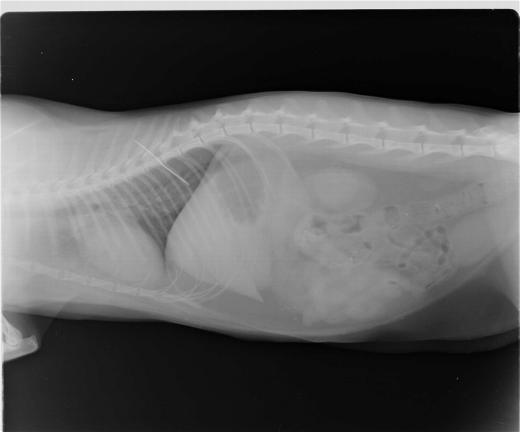

26.10.11 Evelin war aufgefallen, daß sich LaLuna sehr merkwürdig verhielt. Sie schien stumm vor sich hin zu leiden, ließ sich nicht anfassen und bewegte sich kaum noch. Evelin vermisste aus ihrer Näharbeit einen Faden, an dem noch eine 5cm lange Nadel hing. Mit den schlimmsten Befürchtungen brachten wir sie sofort zum Tierarzt nach Lefkas, wofür uns Eddy sein Auto lieh. Mehrere Röntgenbilder brachten Gewißheit - die Nadel steckte in der Speiseröhre.

Alle Versuche sie irgendwie zu entfernen schlugen fehl. Wir entschieden uns nach Empfehlung des Arztes für eine sofortige Notoperation. LaLuna wurde daraufhin für den Eingriff vorbereitet und nachdem der Kollege eintraf wurde operiert. Wir konnten nicht bleiben, denn es wusste keiner der Ärzte, wie lange es dauern könnte. Spät am Abend rief uns Nikos, der behandelnde Tierarzt an und sagte, daß die OP gut verlaufen ist, aber man noch nichts über den Erfolg sagen kann. Am nächsten Tag besuchte ich sie, aber sie war noch zugedröhnt von der Narkose und den Schmerzmitteln. Nikos sagte, daß sie den Bauch und den Magen geöffnet hatten und nach langer Suche endlich den Faden fanden und zu fassen bekamen. Damit haben sie dann vorsichtig die Nadel heraus ziehen können. Es wäre nur eine kleine Verletzung der Speiseröhre enstanden. Diese ist aber trotzdem mit am kritischsten, da nichts durch die Verletzung in den Brustraum gelangen darf. Glücklicherweise würden aber solche Verletzungen binnen weniger Tage verheilen.